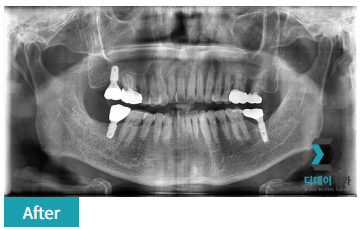

231115

240207